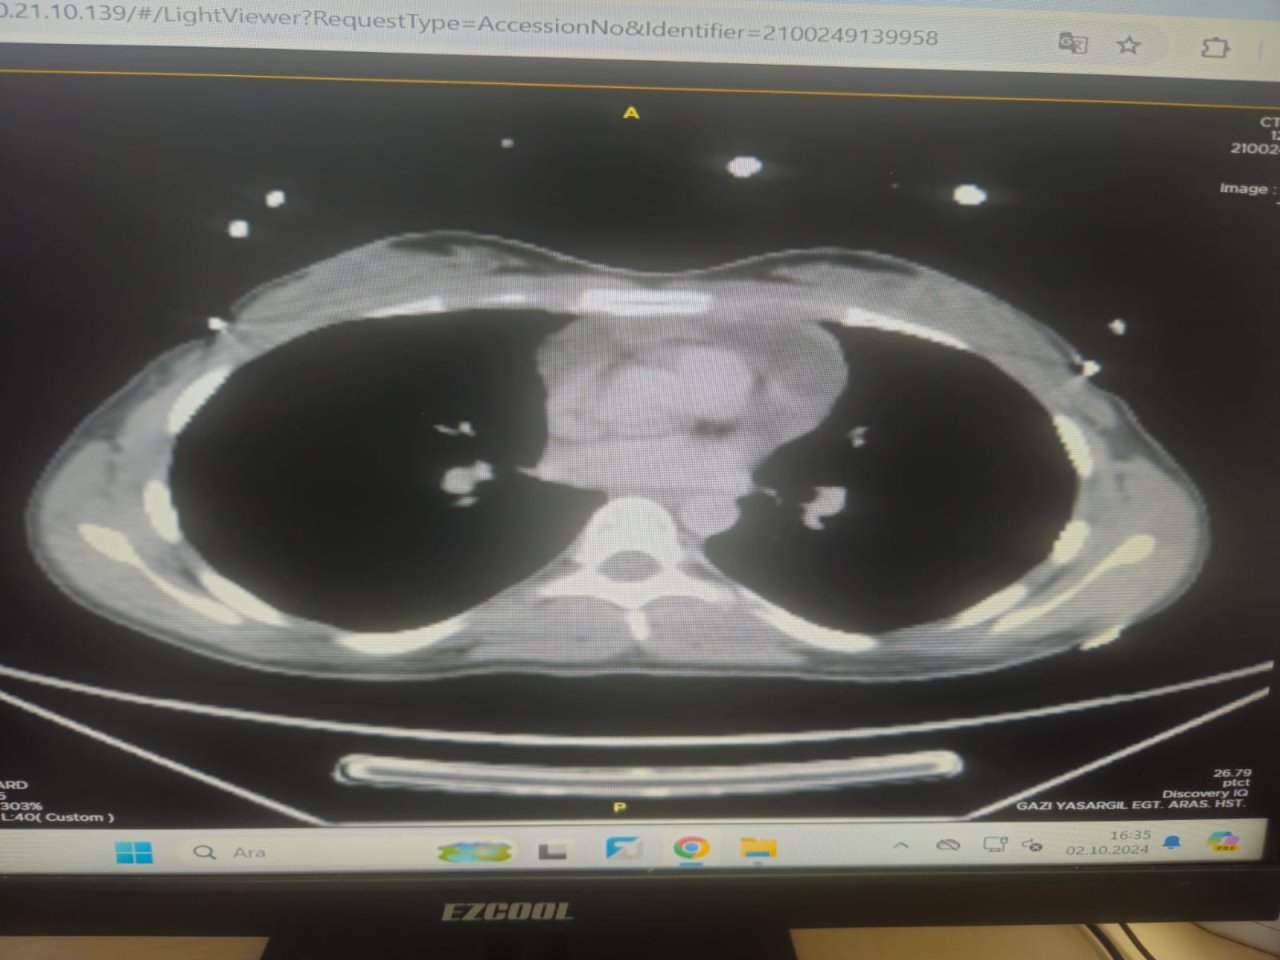

TİGRİS HABER - Diyarbakır Gazi Yaşargil Eğitim ve Araştırma Hastanesi’nde, 21 yaşındaki bir kadın hastaya, göğüs kafesinin ön duvarında bulunan yaklaşık 4 cm’lik kitlenin başarılı bir şekilde çıkarılması için kapalı akciğer ameliyatı (VATS) yapıldı. Ameliyat; Op. Dr. Muhyettin Aslan, Op. Dr. İlyas Konuş ve Op. Dr. Amet Sızlanan’ın oluşturduğu uzman cerrahi ekip tarafından gerçekleştirildi. Hastanın sağlığına kavuşması ve şifa ile taburcu edilmesi, hem hasta hem de ailesi için büyük bir sevinç kaynağı oldu.

Hasta göğüs kafesindeki kitle şikayetiyle polikliniğe başvurdu. Yapılan tetkiklerin ardından ameliyat kararı alındı ve kapalı yöntemle gerçekleştirilen akciğer ameliyatı başarıyla sonuçlandı. Ameliyat ekibi; Video Yardımlı Torakoskopik Cerrahi (VATS) adı verilen bu modern yöntemi kullanarak, göğüs kafesine küçük bir kamera yardımıyla girerek operasyonu tamamladı. Bu teknik, eskiden kullanılan ve göğüs kemiğinin (sternum) açılmasını gerektiren klasik yönteme kıyasla minimal invaziv bir yöntem olmasıyla dikkat çekiyor.